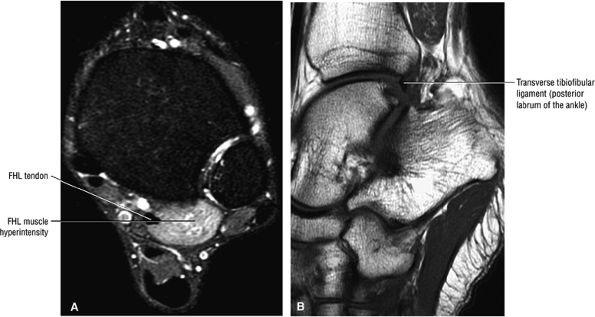

The syndesmotic ligaments consist of the anterior syndesmotic or anterior inferior tibiofibular ligament and the posterior syndesmotic or posterior inferior tibiofibular ligament, the interosseous membrane, and the transverse tibiofibular ligament.

-

The transverse tibiofibular ligament represents the posterior labrum of the ankle and projects inferior to the posterior tibial margin.